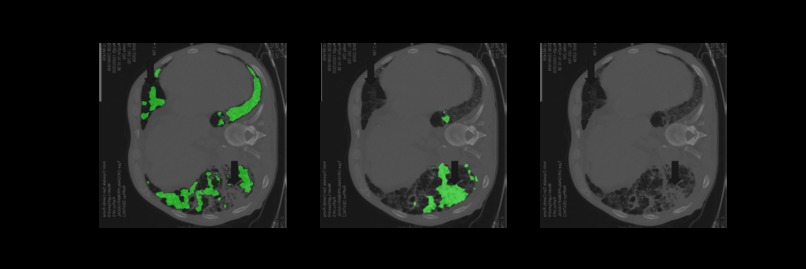

The following is an AI medical segmentation tool for detecting ground-glass, consolidation and pleural effusion in patient lung CT scans. Some reports have shown that ground-glass/consolidation measurements can further enhance the prognosis estimation for Covid-19 patients.